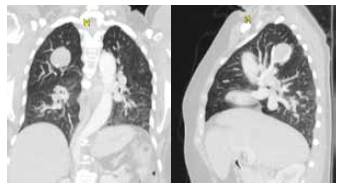

Paciente femenina de 64 años, con antecedentes de hipertensión arterial, bloqueo de rama izquierda, diabetes mellitus no insulinorequiriente y dislipidemia con adecuado control, que consulta con cuadro clínico consistente en dolor torácico inespecífico e intermitente, en hemitórax derecho, de larga data y sin manejo específico, que se exacerba posterior a caída desde su propia altura, asociándose a tos no productiva. Se realiza tomografía computarizada (TC) de tórax con contraste donde se observa un nódulo en el lóbulo superior derecho, de 30 x 26 mm, con bordes bien definidos y atenuación de tejidos blandos, sin captación del medio de contraste; adicionalmente, se encontró un drenaje anómalo de la vena pulmonar superior derecha (figuras 1 y 2).

El diagnóstico suele ser imagenológico. La radiografía de tórax muestra una opacidad redonda, homogénea, bien definida. La tomografia computarizada confirma el hallazgo de una lesión pulmonar redonda u ovoide, bien delimitada, raramente calcificada, con o sin atelectasia o neumonía postobstructiva 8.